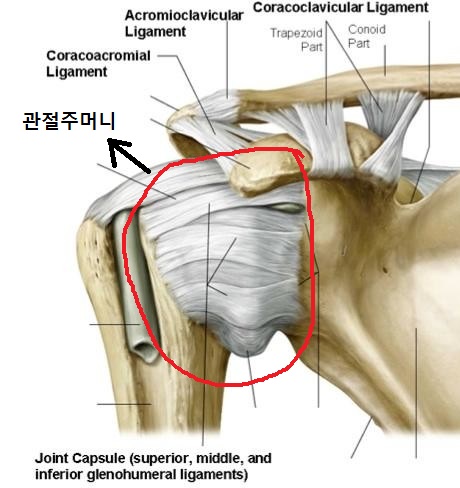

견관절의 관절 포켓 견관절은 불안정한 구조이므로 어깨의 주변부를 많은 결합조직이 덮고 있는데, 이것을 관절 포켓이라고 합니다.

예쁜 관절(왼쪽), 관절내염증(오른쪽)이 여러가지 이유로 염증이 생기면 관절주머니가 두꺼워지고 딱딱해지는 문제가 발생합니다. 관절 내에 있는 윤활액도 부족하여 어깨 관절을 움직이기 어렵고 염증에 의해 움직일 때마다 통증이 유발됩니다.